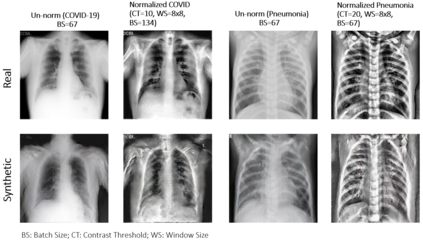

Biomedical image datasets can be imbalanced due to the rarity of targeted diseases. Generative Adversarial Networks play a key role in addressing this imbalance by enabling the generation of synthetic images to augment datasets. It is important to generate synthetic images that incorporate a diverse range of features to accurately represent the distribution of features present in the training imagery. Furthermore, the absence of diverse features in synthetic images can degrade the performance of machine learning classifiers. The mode collapse problem impacts Generative Adversarial Networks' capacity to generate diversified images. Mode collapse comes in two varieties: intra-class and inter-class. In this paper, both varieties of the mode collapse problem are investigated, and their subsequent impact on the diversity of synthetic X-ray images is evaluated. This work contributes an empirical demonstration of the benefits of integrating the adaptive input-image normalization with the Deep Convolutional GAN and Auxiliary Classifier GAN to alleviate the mode collapse problems. Synthetically generated images are utilized for data augmentation and training a Vision Transformer model. The classification performance of the model is evaluated using accuracy, recall, and precision scores. Results demonstrate that the DCGAN and the ACGAN with adaptive input-image normalization outperform the DCGAN and ACGAN with un-normalized X-ray images as evidenced by the superior diversity scores and classification scores.